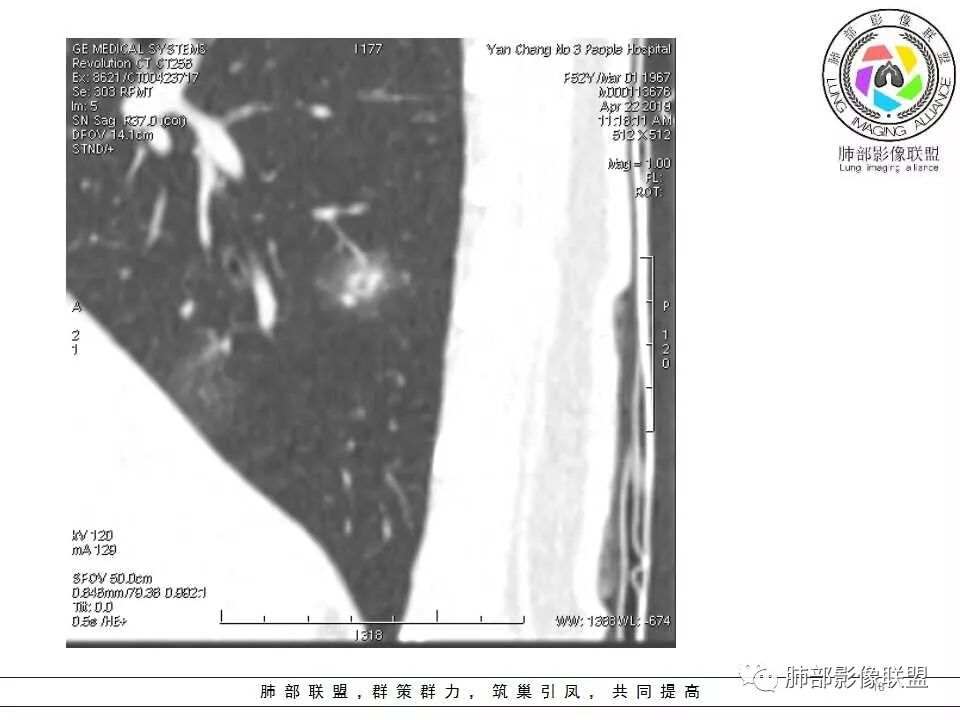

横断位看上去晕很模糊,冠矢状位重建后却比较清晰,所以单次CT检查蛮难定的,中心透亮区一定是空洞吗?我怎么觉得是一支气管壁有增厚,管腔有轻度扩张的支气管,第一感觉还是炎性结节吧,PC可能大,一定要否定腺癌也不敢,一个月左右复查。

体检发现肺部结节,右下肺混合密度结节,结节中心空泡,壁光滑,结节边缘模糊,血管在结节内增粗,矢状位前基底段还有一片磨玻璃影,所以考虑良性结节可能,炎性肉芽肿?抗炎后复查。腺癌合并炎性改变待排。

连续层面显示这个应该是空泡,或者小空洞,远端没有,近端也没有,周围环形软组织增厚。而空泡,影像上只是根据5mm界线,病理上不一定。

问一个问题,肺动脉肺静脉?为啥?

静脉,夹角90,周边没气管伴行。

静脉吧,动脉同时会伴有一根气管

这些呢?为啥?

动脉,有支气管伴行

伴有支气管

南边:

假如这是含气支气管,伴随的哪条动脉呢?近端从哪来?为啥环形壁增厚而又不均匀?都不太符合,所以支持空泡或小空洞。

上次刘纯老师提出,空泡征是一个影像征象,不是一个病理征象,我比较支持,他就是一个影像上的小低密度腔,原因很多,但是影像上与小的空洞表现区分不了。其中的原理:有一条是内容物排出后的残腔,其实也是空洞的原理。